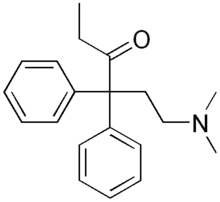

The first fully synthetic opioid was meperidine (later demerol), found serendipitously by German chemist Otto Eisleb (or Eislib) at IG Farben in 1932.[228] Meperidine was the first opiate to have a structure unrelated to morphine, but with opiate-like properties.[199] Its analgesic effects were discovered by Otto Schaumann in 1939.[228] Gustav Ehrhart and Max Bockmühl, also at IG Farben, built on the work of Eisleb and Schaumann. They developed "Hoechst 10820" (later methadone) around 1937.[230] In 1959 the Belgian physician Paul Janssen developed fentanyl, a synthetic drug with 30 to 50 times the potency of heroin.[211][231] Nearly 150 synthetic opioids are now known.[228]